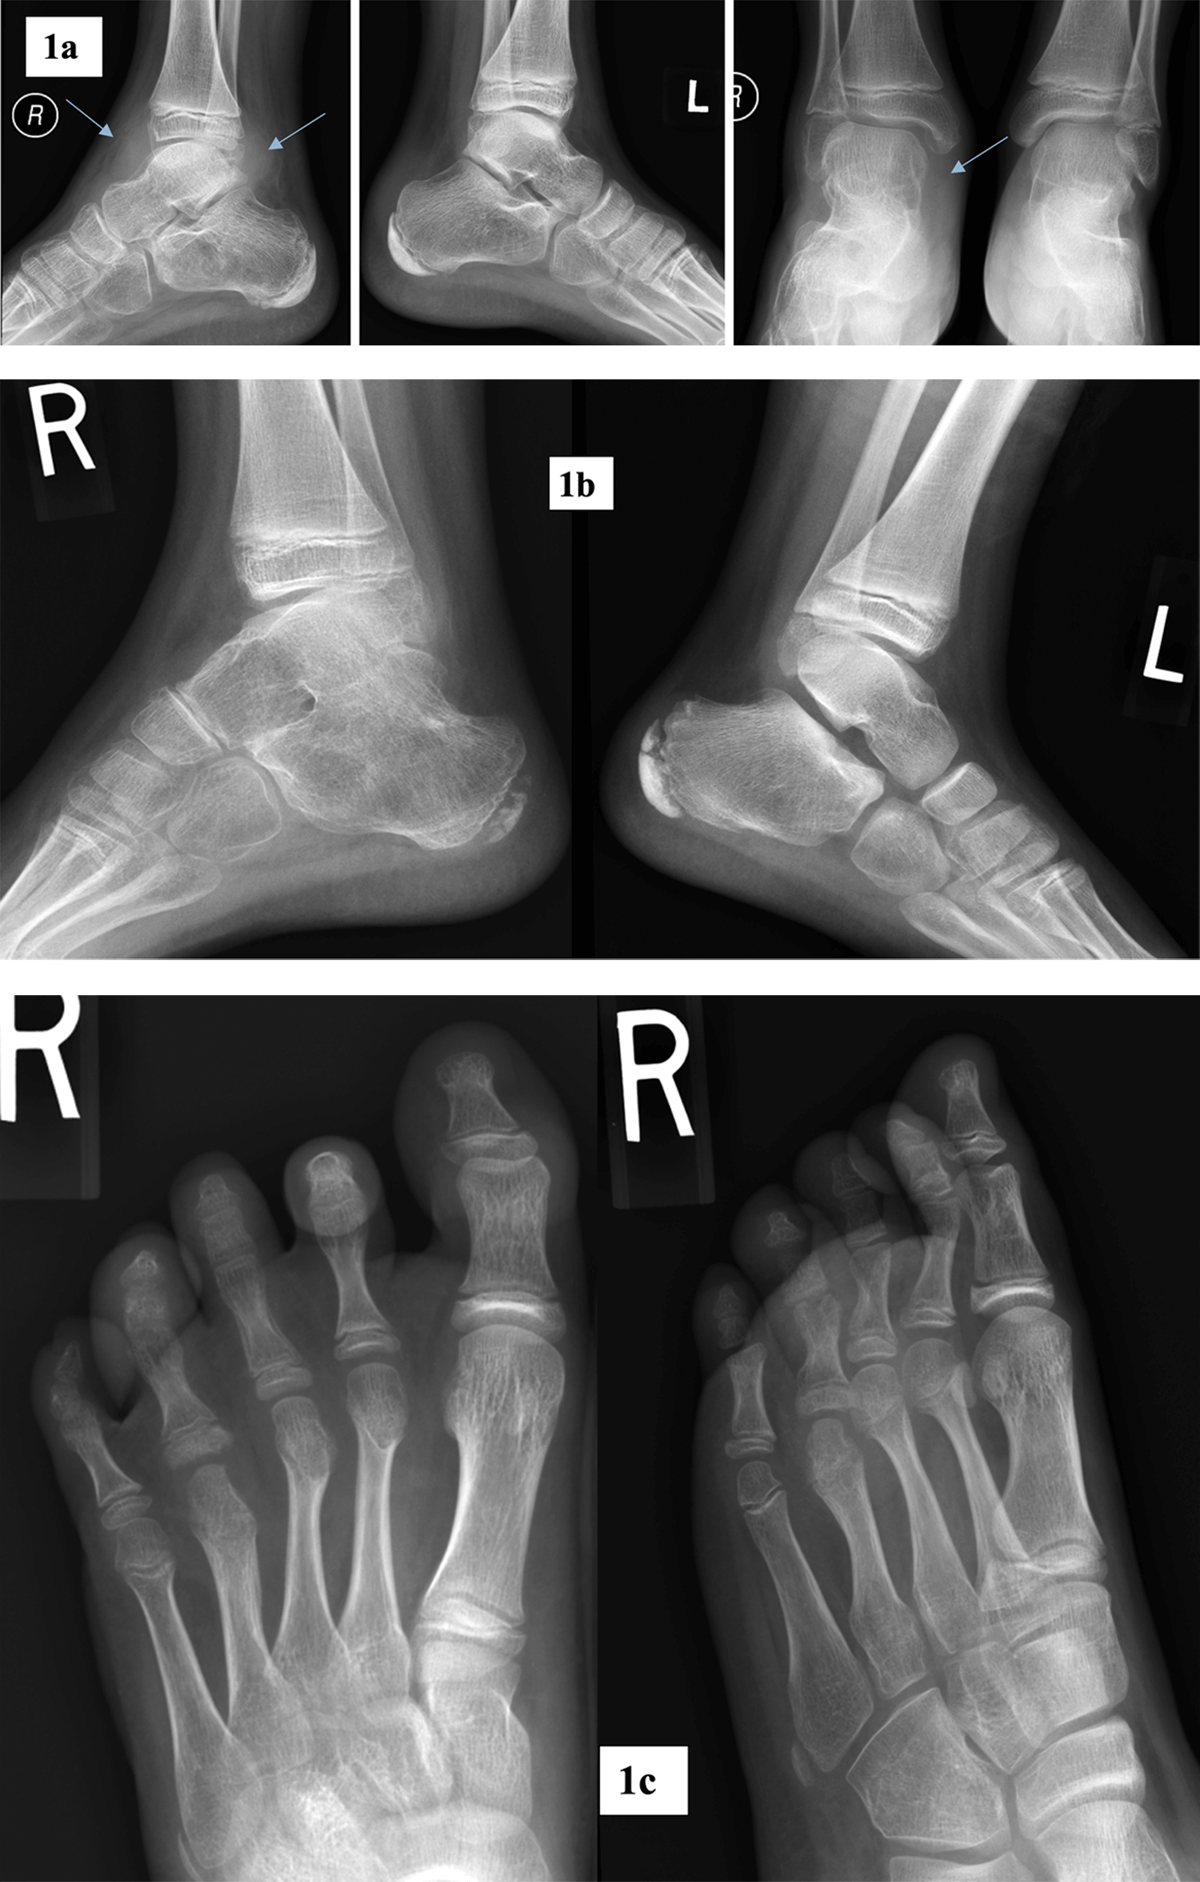

Figure 1

Radiographic abnormalities of foot and ankle.

a. Antero-posterior and lateral radiographs of both ankle joints in a 12-year-old male patient with JIA. Marked soft tissue swelling at the level of right ankle joint (arrows).

b. Lateral radiographs of ankle joints in a 9-years-old male with JIA. Marked osteoporosis of right talar and calcaneal bones with ankylosis in subtalar joint. Talonavicular joint space narrowing with subchondral sclerosis. Normal left ankle joint.

c. Antero-posterior and oblique radiographs of the right foot in a 9-year-old female with JIA. Erosions and subchondral cysts in fourth MTP and PIP joints, periarticular osteoporosis, soft tissue swelling at the level of MTP2 joint.